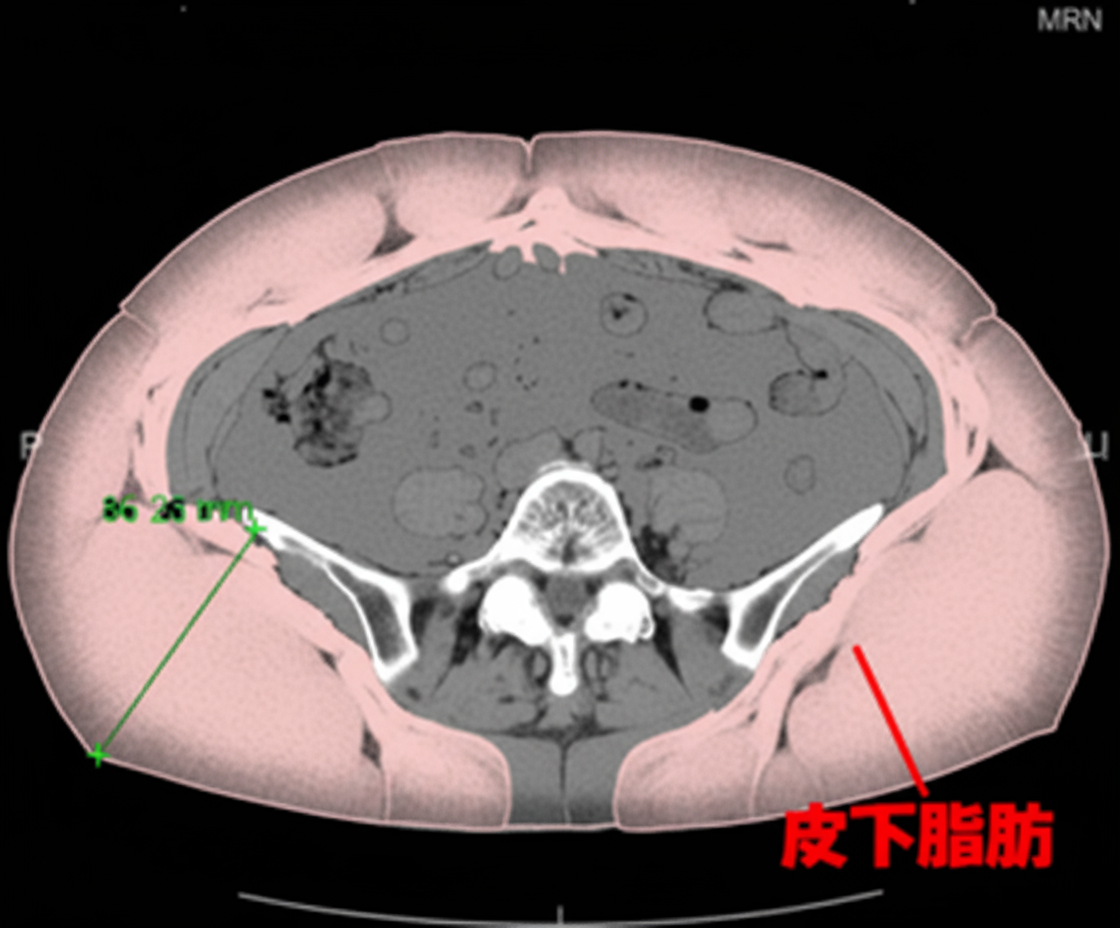

内臓脂肪計測(40歳以上の方)

内臓脂肪≧100㎠は危険!

でも、上の図からも判るように腹囲は必ずしも内臓脂肪量を反映しないのです。 自分のお腹の中身を知って、今後の健康管理に役立てましょう!

脂肪には「内臓脂肪」と「皮下脂肪」があります。「内臓脂肪」は、過剰に蓄積すると動脈硬化を進めて脳卒中や心筋梗塞を起こす原因になります。(皮下脂肪優位型の方の動脈硬化リスクは高くありません。)

日本肥満学会では、へその位置の内臓脂肪面積が100c㎡を超えた場合を病気としての「肥満症」と判定しています。検査はCTによるへそ断面の撮影で3分ほどで終了します。この機会に一度、自分の動脈硬化リスクを見つめ直してみませんか。

なお、 この検査は、へそをねらってごく少ない照射量で撮影するので、普通のCT撮影に比べてはるかに安全ですが、念のため対象者は40歳以上の方とさせていただきます。 腹部CTをお受けになる際一緒に測定するのが、特にお勧めです。